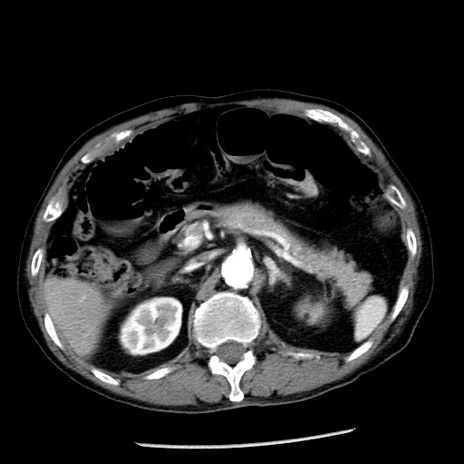

症例26(横断像)

【症例】80歳代男性

【主訴】嘔吐

【現病歴】昨晩2回嘔吐あり、今朝になっても嘔吐あり。来院。

【既往歴】胃潰瘍

【身体所見】意識清明、BT 37.6℃、BP 166/95mmHg、HR 100bpm、SpO2 97%、腹部:平坦・軟、腸蠕動音聴取良好、圧痛なし。

【データ】WBC 21900、CRP 1.46